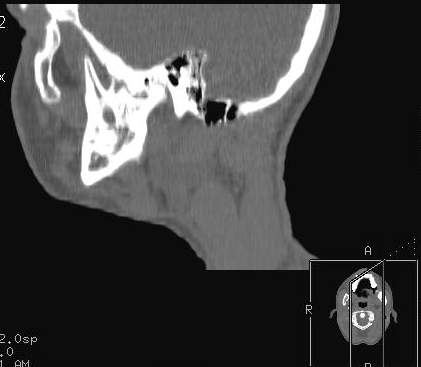

Пациент В., 13 лет. Диагноз: Костный анкилоз левого височно-нижнечелюстного сустава (ВНЧС), левосторонняя микрогения. Болеет с 2-х летнего возраста. Возможная причина развития анкилоза – воспалительный процесс (в первые 1,5 года жизни часто болел простудными заболеваниями, травму родители отрицают). В 3 и 5 лет проводилась редрессация – безуспешно. Прилагаются: ортопантомограмма, кадры СКТ с 3Д реконструкцией. Вопросы: определение тактики лечения – вид и сроки реконструктивно-пластической операции (этапов операции), а именно – неоартропластики и устранения микрогении, медикаментозная терапия в до- и послеоперационный период, ортодонтическое лечение.